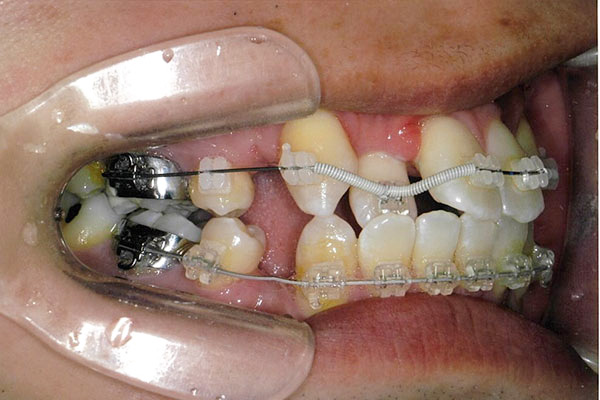

症状八重歯+二重歯列による噛み合わせ不具合

6ヶ月後